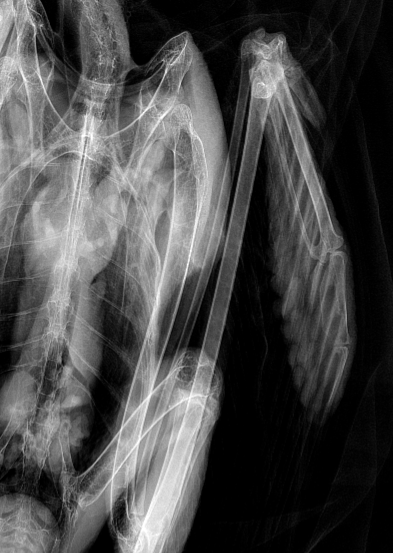

Because the swelling made it difficult to feel the bones, radiographs (X-rays) were taken. These images showed a dislocation at the metacarpophalangeal joint, the joint where the “finger” of the wing connects to the hand bones.